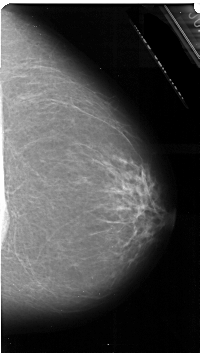

A_1055_1.LEFT_CC

LEFT_CC LINES 5401 PIXELS_PER_LINE 3211 BITS_PER_PIXEL 16 RESOLUTION 42 OVERLAY